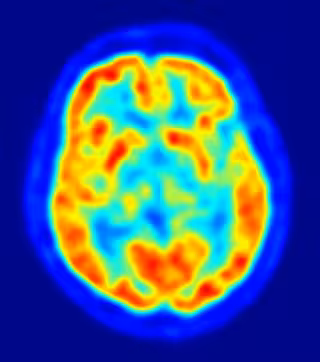

cerebro, recurso, neuronas